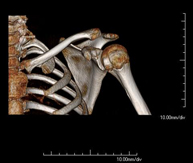

- TC d'espatlla

Exploració radiològica que mitjançant un sistema de raigs X i detectors que giren al voltant del pacient i que reconstrueixen les imatges per ordinador (TC Multidetector), permet l'estudi detallat dels ossos, els músculs i les articulacions de l'espatlla. - TC de colze